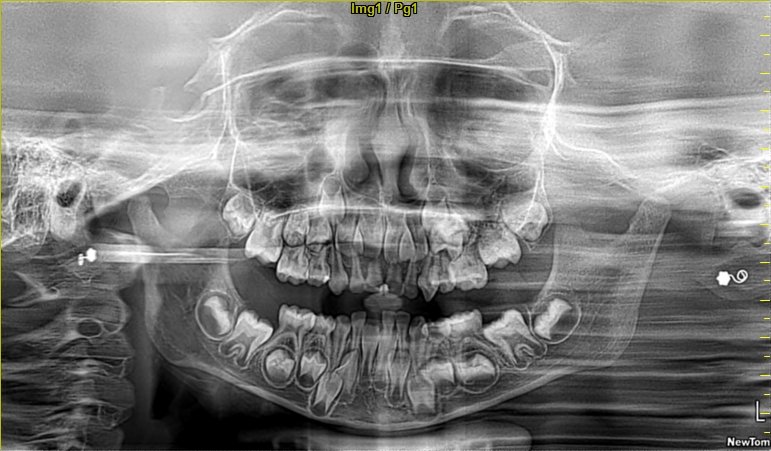

Panoramic X-Rays

Provides a full view of the entire mouth, jaw, and sinuses.